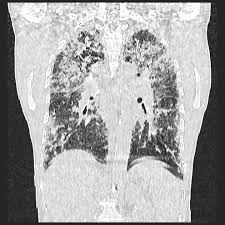

Chronic Hypersensitivity Pneumonitis Radiology Case Radiopaedia Org Ill Defined Centrilobular Ground Glass Opacities R Hypersensitivity Radiology Chronic